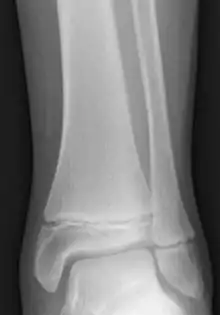

صفيحة مشاشية[1] (بالإنجليزية: Epiphyseal plate) أو صفيحة النمو (بالإنجليزية: growth plate) ، هي صفيحة من غضروف زجاجي تقع في كل كردوس في نهاية طرفيّ العظام الطويلة. توجد الصفيحة في الأطفال والمراهقين [2]؛ وفي البالغين ممن توقف لديهم النمو، فتُستبدال الصفيحة بخط مشاشي.

العيوب في نمو الصفيحة المشاشية وانقسامها المستمر ممكن أن يؤدي إلى اضطرابات في النمو.[2] الخلل الأكثر شيوعًا هو الودانة، في حالة وجود خلل في تكوين الغضروف، الودانة هي أشهر سبب للقزامة. كسور سالتر هاريس هي عبارة عن كسور تتضمن الصفيحة المشاشية ولذلك تشير إلى التدخل في النمو والطول. مرض أسجود سكالتر ينتج عن الإجهاد على الصفيحة المشاشية في قصبة الساق مما يؤدي إلى نمو العظام الزائدة ووجود تورم مؤلم في الركبة.